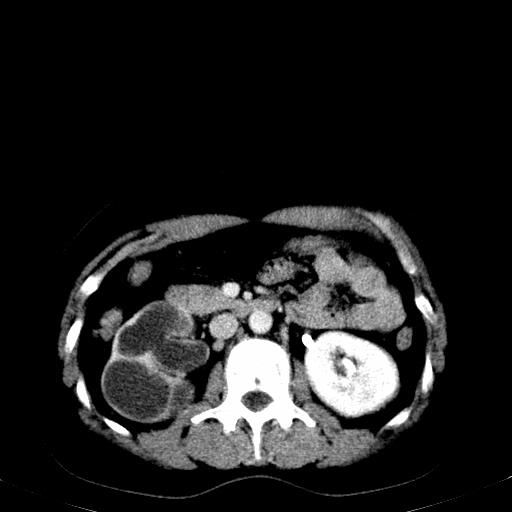

患者体检发现右肾体积增大,怀疑右肾积水

右肾多发囊肿,左肾、左输尿管结石

右肾重度积水,以肾盏积水明显,有分隔,上段输尿管轻度扩张,管壁增厚,考虑肾结核可能,请结合尿检查,胸部拍片排除肺结核。

左肾不像是结石吧,是不是做过造影啊

左肾哪里有结石???

第一个序列应该是延迟图像吧;

左肾不是结石,是造影后改变.右肾积水,功能仅存.